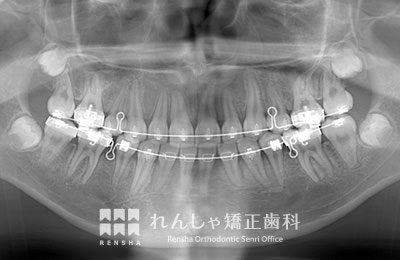

中高生

永久歯列はほぼ完成してしますが、歯列を側方だけでなく後方へも拡大し、埋まっていた右上奥歯を引っ張り出しています。

| 主訴 | 埋まったままでてこない歯がある |

|---|---|

| 診断名 | Angle Class II 小臼歯の埋伏と叢生を伴う上顎前突 |

| 初診時年齢 | 13歳5か月 |

| 装置名 | マルチブラケット装置 |

| 抜歯非抜歯 | 非抜歯 |

| 治療期間 | 2年3か月 |

| 費用の目安 | 約82万円+消費税(検査料金、都度の処置費用等も合わせた総額) |

| リスク副作用 | 歯の移動に伴う軽微な歯根吸収、歯槽骨吸収、歯肉退縮(本症例では軽度の歯根吸収を認めた)、矯正器具装着中のカリエスリスク増大(本症例ではカリエス発生無し) |